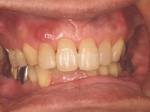

両側5歯症例

両側5歯症例両側5歯症例両側5歯症例 主訴-義歯のバネが壊れて手前の歯が痛んできた。 術前(旧義歯装着、鏡像) 術前(下顎粘膜面、鏡像)術前(下顎粘膜面、鏡像)術前(下顎粘膜面、鏡像) 術前レントゲン術前レントゲン術前レントゲン 術前口腔内(正面観)術前口腔内(正面観)術前口腔内(正面観)

術後(鏡像)術後(鏡像)術後(鏡像) 術後口腔内(正面観)術後口腔内(正面観)術後口腔内(正面観)もう入れ歯は要らなくなりました。 術後レントゲン術後レントゲン術後レントゲン